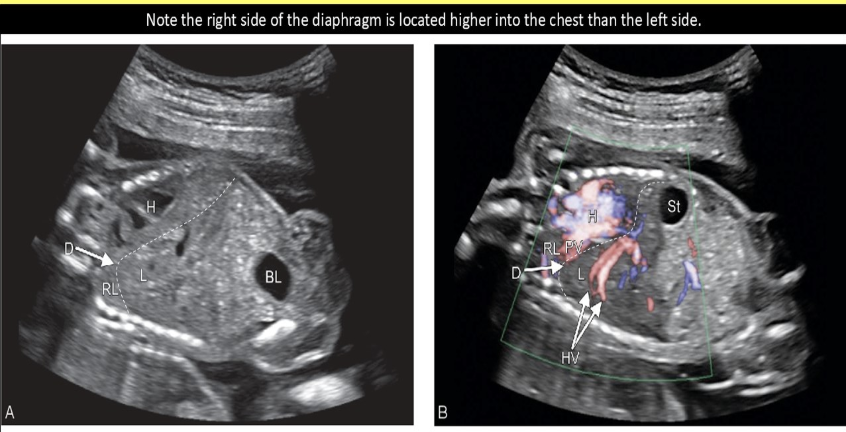

which fetal abn mimics the sono appearance of diaphragmatic hernia

.

a) situs inversus

b) situs solitus

c) duodenal atresia

d) [diaphragmatic] eventration

d) eventration